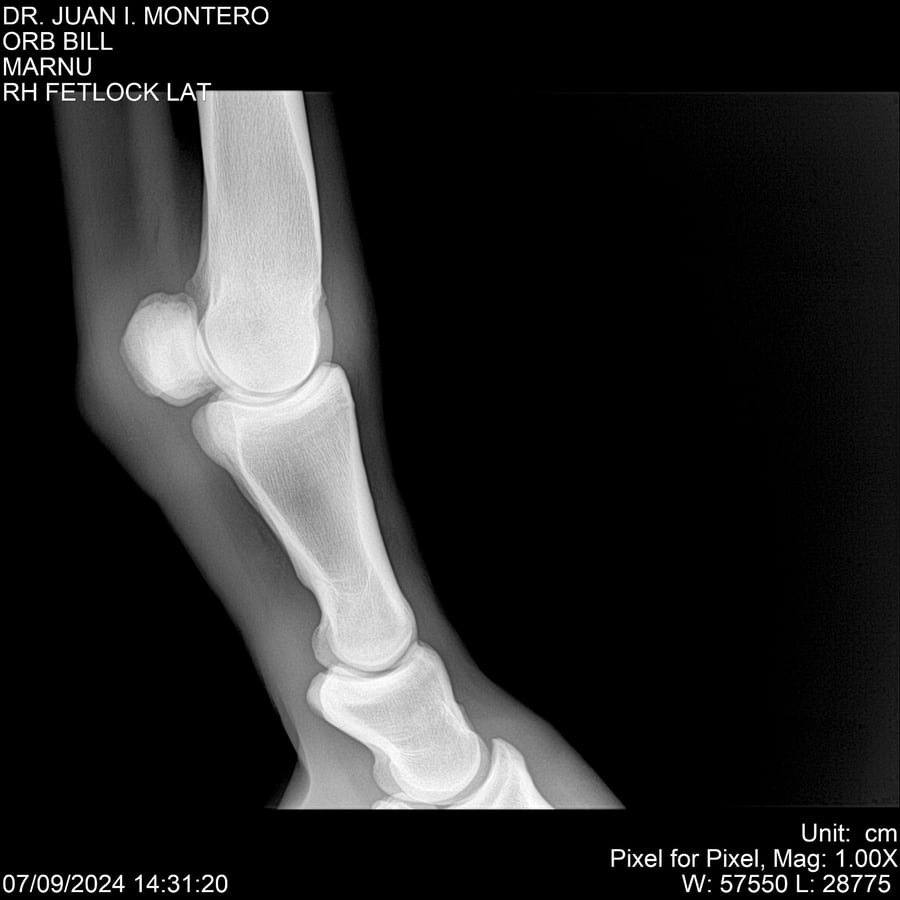

LOTE 7, ORB BILL 🔥 🔥 🔥 Lote Anterior Volver al remate Lote Siguiente Ficha Contacto Montevideo - Ficha del Lote Identificador: #282523 Categoría: Yeguarizos Montevideo - 83 Visualizaciones ClicData Contacto Empresa: Abelenda N. R., Walter Hugo Nombre*: Teléfono* : E-mail* : Mensaje Enviar Registrese gratis Este contenido Exclusivo está disponible sólo para usuarios registrados Ingresar